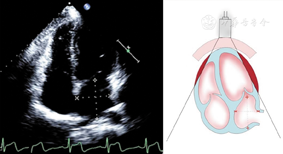

(1)心尖四腔心切面(图7图8图9图10图11图12图13图14图15图16图17图18图19)

心尖四腔切面,在舒张末期测量右心室长径、右心室中份和基底部横径